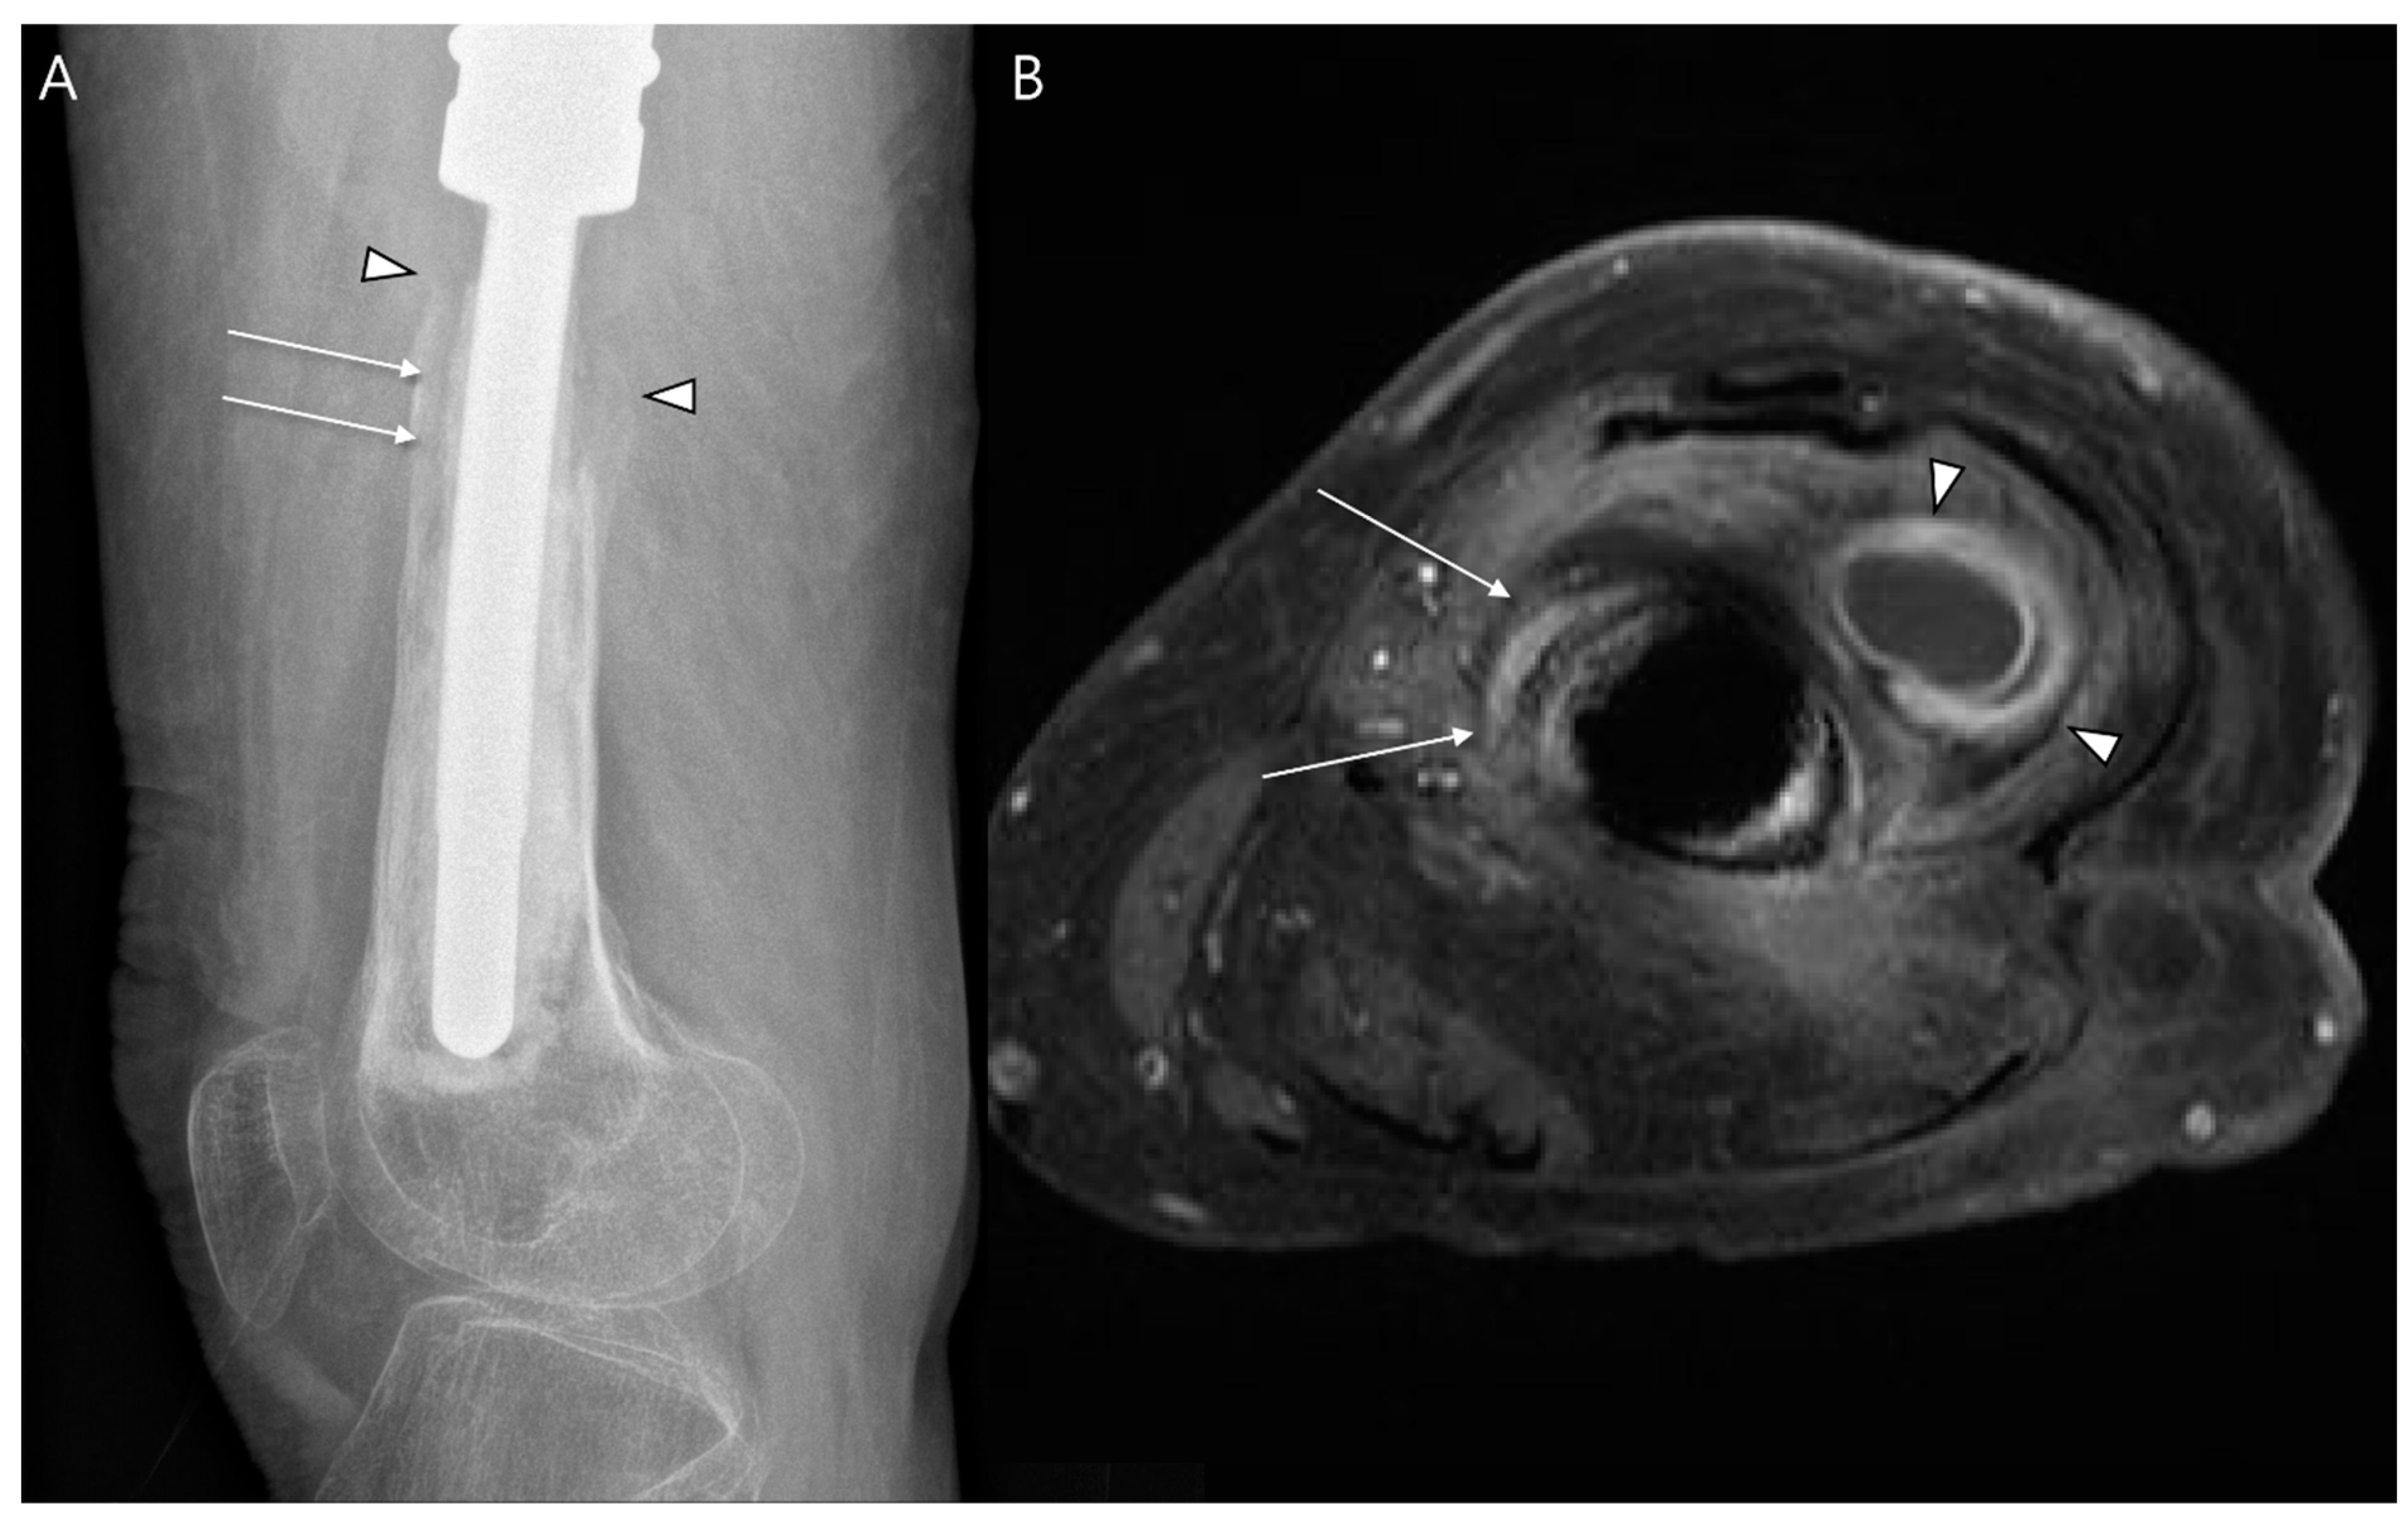

- Cyteval, C.; Bourdon, A. Imaging orthopedic implant infections. Diagn. Interv. Imaging 2012, 93, 547–557. [Google Scholar] [CrossRef]

- Simpfendorfer, C.S. Radiologic Approach to Musculoskeletal Infections. Infect. Dis. Clin. 2017, 31, 299–324. [Google Scholar] [CrossRef]

- Shah, A.; Cardoso, F.N.; Souza, F.; Montreuil, J.; Pretell-Mazzini, J.; Temple, H.T.; Hornicek, F.; Crawford, B.; Subhawong, T.K. Failure Modes in Orthopedic Oncologic Reconstructive Surgery: A Review of Imaging Findings and Failure Rates. Curr. Oncol. 2024, 31, 6245–6266. [Google Scholar] [CrossRef]